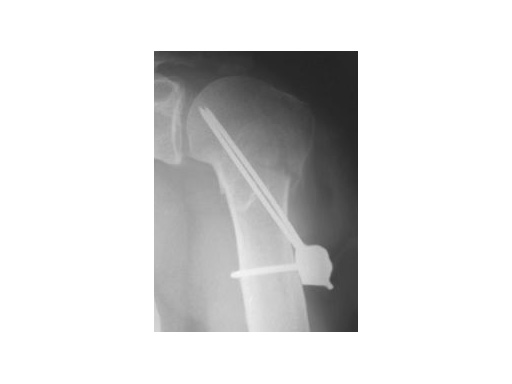

62 year old female patient

Fig 1

Accident

Fig 2

postoperative